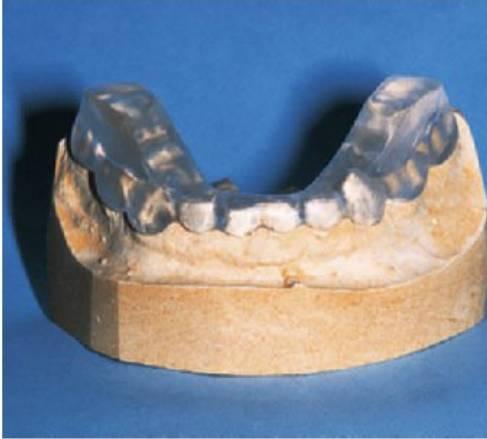

El término «indiferencia al dolor» en estos casos es erróneo, ya que la indiferencia implica una falta de atención cerebral o una disfunción cognitiva. Los pacientes con «indiferencia» reciben correctamente los estímulos dolorosos, pero fallan en la reacción habitual de defensa que es la retirada. Sin embargo, en los pacientes con «insensibilidad al dolor», se preservan los reflejos de los tendones profundos porque los controlan fibras mielinizadas de gran diámetro y la falta de percepción del dolor se debe a una neuropatía periférica (fig. 8.21).

Diagnóstico

El diagnóstico de estos cuadros suele hacerse por exclusión y por la observación minuciosa del niño. No es infrecuente que transcurran algunos meses hasta que se realice un diagnóstico correcto y, en ausencia de otras enfermedades, los padres o los cuidadores pueden sospechar incorrectamente de abuso en el niño o de padecer el síndrome de Münchhausen. La incapacidad para reconocer o sentir el dolor hace que estos niños se avulsionen los dientes y se infrinjan extensos traumatismos en las encías, la lengua o la mucosa, bien con los dedos o mordiendo y masticando.

La ulceración autoinfligida (ulceración simulada) se puede producir también como un hábito (parecido a morderse las uñas), pero también como una manifestación de trastornos psicológicos.

Tratamiento

- Tallado selectivo de las cúspides de los dientes o reconstrucción «en cúpula» de la meseta oclusal con resina composite para obtener una superficie lisa.

- Férulas acrílicas o férulas de plata sobrepuestas para evitar ulceraciones importantes de la lengua o los dedos.

- Como última opción, puede requerirse la extracción de los dientes en los casos más graves.

El tratamiento inicial de los niños pequeños suele requerir su inmovilización para impedir que se autolesionen. Incluso con los padres más atentos, resulta imposible la vigilancia constante y los niños seguirán lesionándose incluso cuando se les proporcionen los mejores cuidados. Se precisa la intervención de terapeutas ocupacionales que ayuden a los padres y puedan acondicionar los hogares con medidas protectoras, como el uso de prendas de ropa almohadilladas, férulas para los brazos, cascos y otros dispositivos de protección. Si aparecen laceraciones en la lengua y en otros tejidos, los protectores bucales y otros dispositivos impedirán la oclusión de los dientes. Es mejor colocar aparatos en la arcada inferior que en la superior. En los casos graves en los que no se puede tratar la mutilación, se ha utilizado toxina botulínica A (Botox) para paralizar selectivamente los músculos elevadores principales de la mandíbula (pterigoideo medial y masetero).